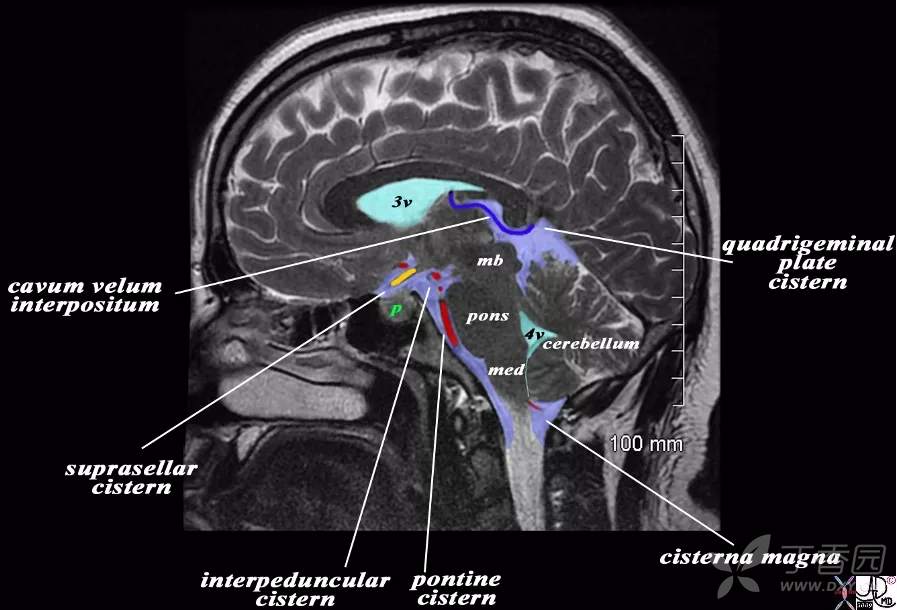

由于脑池和脑室内均为低密度的脑脊液,有时影像上二者易于混淆。因此,熟悉脑池的断层影像解剖,对病变的影像学定位诊断至关重要。MRI 可较好地显示脑池及内含结构。CT 平扫即可观察较低密度的脑池。

大脑大静脉池 Galen's vein cistern 是四叠体池向上的延续,居第三脑室的后方,上抵胼胝体压部。池内前有松果体,后有大脑大静脉。

四叠体池

四叠体池 quadrigeminal corpus cistern 又称上池 superior cistern ,居中脑四叠体后面与小脑蚓部前缘之间,两端向外连于环池翼部,向前外通环池本部。四叠体池和环池位于小脑幕切迹内,幕上或幕下的病变可经这些脑池延伸。例如,小脑幕切迹疝可使这些脑池变窄或消失。

鞍上池

鞍上池 suprasellar cistern 为CT 和MRI 等影像学用语。鞍上池位于蝶鞍上方,是交叉池、脚间池或桥池在轴位扫描时的共同显影。

1. 交叉池 chiasmatic cistern 位于视交叉周围,外界是颈内动脉,前方有大脑前动脉和前交通动脉。

2. 脚间池 interpeduncular cistern 位于视交叉后方、脚间窝前方,内有动眼神经、大脑后动脉水平段等。

3. 桥池 pontine cistern 位于斜坡与脑桥基底部之间,内有基底动脉,向两侧与脑桥小脑角池延续。

小脑延髓池

小脑延髓池 cerebellomerlullary cistern 又名枕大池,位于小脑半球后下方、延髓背面和枕鳞下部前方。池内有小脑下后动脉经过。

延池

延池 medulla oblongata cistern 位于延髓腹侧与斜坡之间。左、右椎动脉在池内相互接近合成基底动脉。小脑下后动脉在池内起自椎动脉,舌下神经经延池进入舌下神经管,舌咽、迷走及副神经经此池向外侧至颈静脉孔。